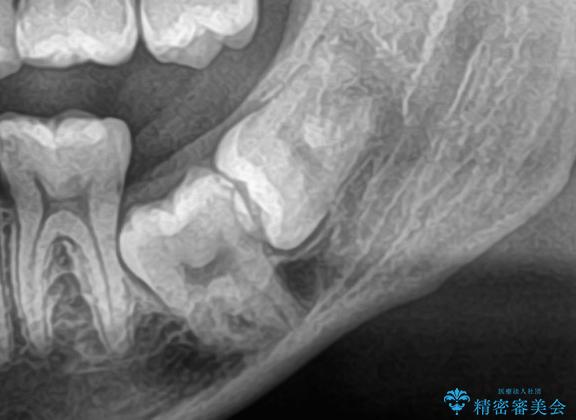

- 当院で矯正治療予定の患者さんです。下顎水平埋伏智歯による下顎第二大臼歯の歯周病やう蝕のリスクを考慮し抜歯をする事になりました。

今回の下顎水平埋伏智歯は歯茎と骨に埋まっていたので、麻酔をした後に歯茎を切開し骨を削って抜歯をしています。抜歯後、糸を縫って1週間後に抜糸に来ていただいています。抜歯後1週間は痛みとお顔の腫れがあり、度合いには個人差があります。